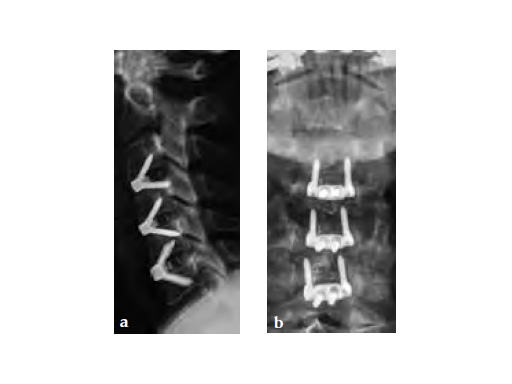

Case provided by Frank Kandziora, Frankfurt, Germany

59-year-old female with neck pain and right radicular arm pain C5 and C6 and weakness during walking. An MRI was performed and a severe DDD with soft spinal stenosis C3C6 was diagnosed. Neurophysiology revealed myelopathic spinal cord changes. Decompression and stabilization C3/4, C4/5, and C5/6 using Zero-P was performed. After surgery the patient was nearly free of pain, had no complains regarding dysphagia, and was neurologically improved.